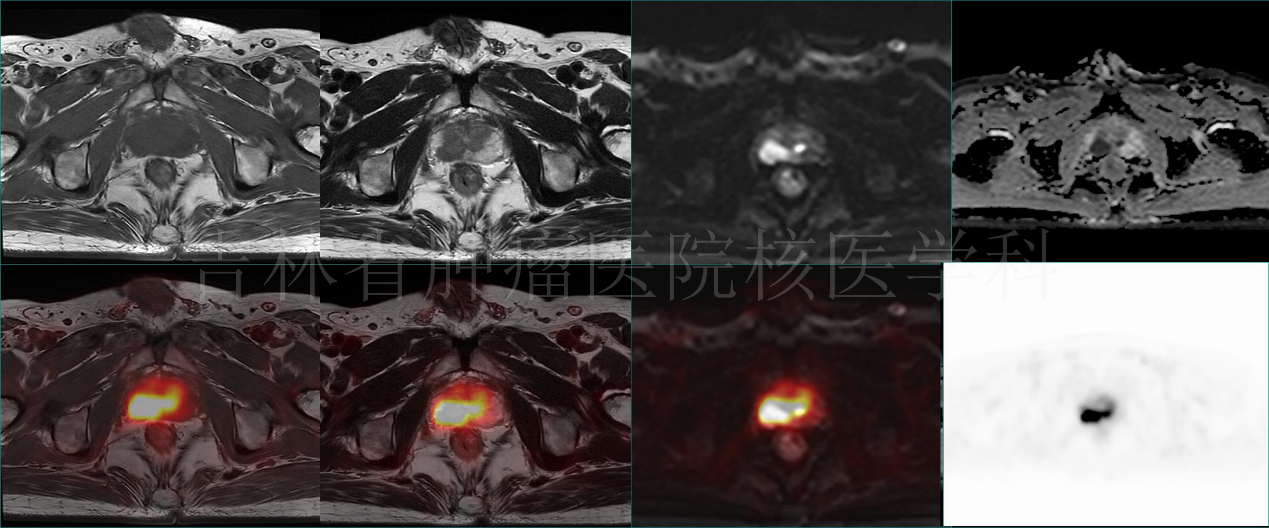

病例3 PET/MR诊断前列腺癌:前列腺右侧外周带结节,T1WI呈等信号,T2W呈稍高信号,DWI呈高信号,ADC值减低,伴18F-FDG摄取增高(病理结果:前列腺癌)